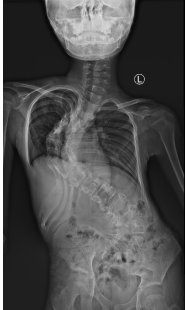

此次来我院的四名藏族患儿,均为重度脊柱侧弯,最严重者脊柱侧弯Cobb甚至高达120多度,脊柱严重变形,手术难度及风险高,在当地难以治疗。深圳市儿童医院骨科党支部心系藏族同胞需求,迎难而上,针对每一位藏族患儿的病情制定了个性化、精细化的诊疗方案。从术前详细的脊柱畸形评估、三D打印重建,到术中精准的脊柱畸形截骨矫正,再到术后全面科学的康复指导,先后成功为藏族患儿进行了脊柱侧弯矫正,帮助他们挺直了脊梁。

看到藏区孩子们经过治疗后,原本弯曲的脊柱逐渐挺拔,罗新乐书记强调,深圳市儿童医院始终秉持“一切为了孩子”的宗旨,积极发挥儿童医疗中心的辐射作用,为包括藏族同胞在内的广大患儿提供高质量的医疗服务。医院将继续加强藏区医疗帮扶,守护民族未来脊梁,为孩子们的健康成长保驾护航!